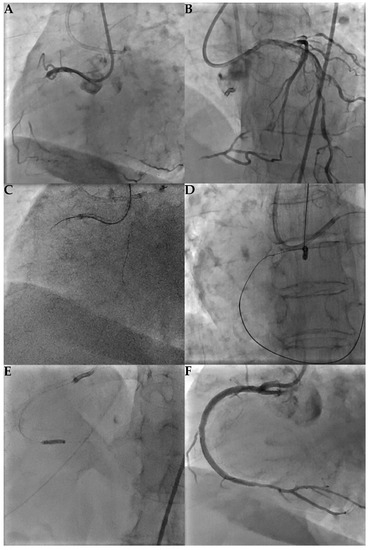

6.2. Retrograde

7. Complications Management

- Balloon occlusion proximal to the perforation side to prevent bleeding. The balloon size should be 1:1 with the target vessel and inflated at low pressure. To confirm successful execution contrast injection should be performed.

- Intravenous fluids and pressors.

- Pericardiocentesis in case of tamponade.

- Urgent cardiothoracic surgery consults when percutaneous techniques fail.